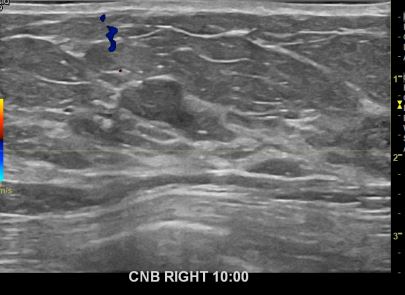

아산유외과개원후656번째유방암진단

상기환자 외부검사상 이상소견으로 내원하신 60대여성으로 우측에 의심스러운혹 조직검사시행해 유방암 진단되었습니다.